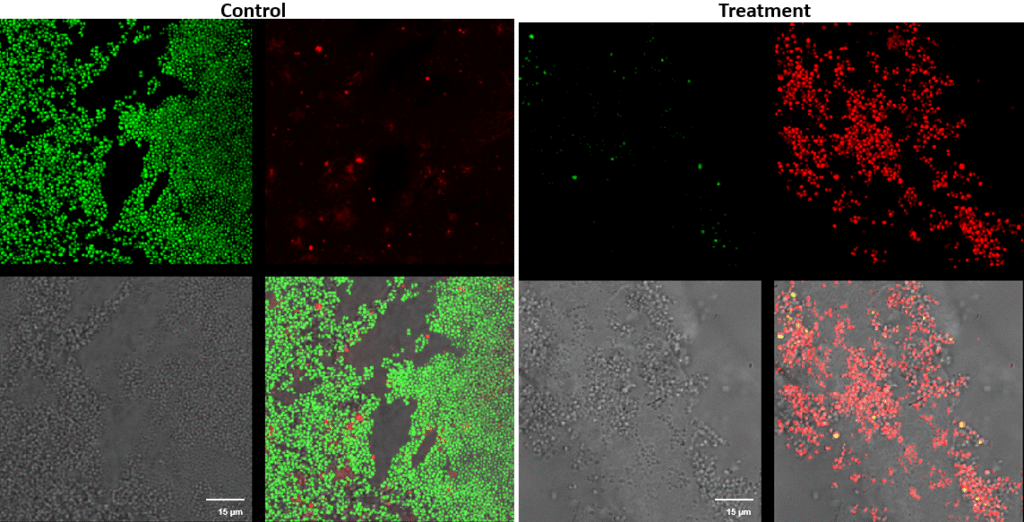

Streptococcus canis – Superficial fluorescence microscopy. Each image is divided into four quadrants: the upper left quadrant shows the green channel highlighting live bacteria; the upper right shows the red channel highlighting dead bacteria; the bottom right shows the merged green and red channels indicating live and dead bacteria; and the bottom left illustrates the bright field image. Bright green represents bacteria with intact membranes (live), red represents bacteria with compromised or dead membranes, and yellow represents bacteria with partially compromised membranes. Scale bar: 15 µm.

Pseudomonas aeruginosa – Superficial fluorescence microscopy. Microscopic imaging of Pseudomonas aeruginosa inoculated on the corneal surface and treated with UV-C for 15 seconds at a 10 mm distance. The images show clear bacterial membrane disruption and reduced viability, demonstrating the antimicrobial effectiveness of UV-C treatment on the superficial corneal layer.

Each image is divided into four quadrants: the upper left quadrant shows the green channel highlighting live bacteria; the upper right shows the red channel highlighting dead bacteria; the bottom right shows the merged green and red channels indicating live and dead bacteria; and the bottom left illustrates the bright field image. Bright green represents bacteria with intact membranes (live bacteria), red represents bacteria with compromised or dead membranes, and yellow represents bacteria with partially compromised membranes. Scale bar: 15 µm.

Panel with fluorescence microscope images of Pseudomonas aeruginosa (A & B), Streptococcus canis (C & D), Staphylococcus pseudintermedius (E & F), and a polymicrobial mix (G & H) inoculated superficially and treated with UV-C for 15 seconds.

Control samples are represented by images A, C, E, and G, and treated samples by images B, D, F, and H.

Each image is divided into four quadrants: the upper left quadrant shows the green channel highlighting live bacteria; the upper right shows the red channel highlighting dead bacteria; the bottom right shows the merged green and red channels highlighting live and dead bacteria; and the bottom left illustrates the bright field image. Bright green represents bacteria with intact membranes (live), red represents bacteria with compromised or dead membranes, and yellow represents bacteria with partially compromised membranes. Scale bar: 15 µm.